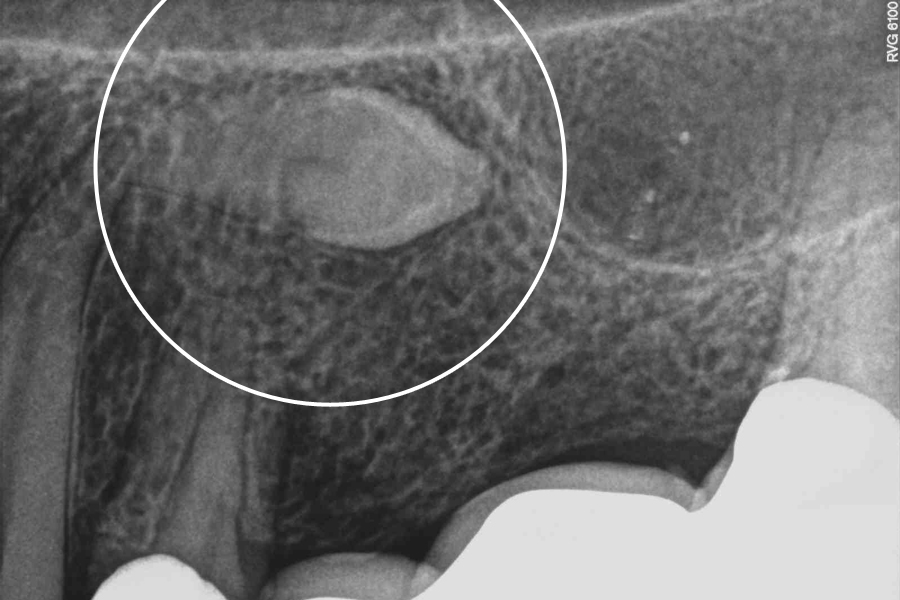

Ząb zatrzymany to w pełni wykształcony ząb stały, który po okresie fizjologicznego wyrzynania pozostaje w utkaniu kostnym szczęk lub żuchwy. Może być on zatrzymany całkowicie, gdy jest otoczony kością ze wszystkich stron lub zatrzymany częściowo, gdy ma koronę poza kością pokrytą jedynie dziąsłem.

Rozpoznanie zęba zatrzymanego opiera się na badaniu rentgenowskim.